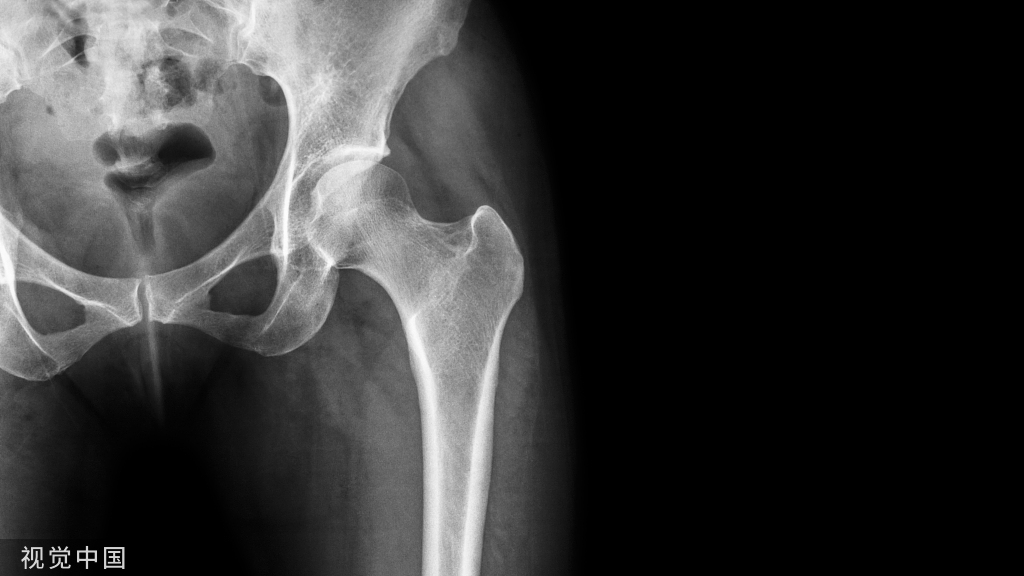

我们先来分析一下胫骨近端的解剖,容易出现哪些移位,一屈曲膝关节,则容易出现外翻,屈曲,上移。